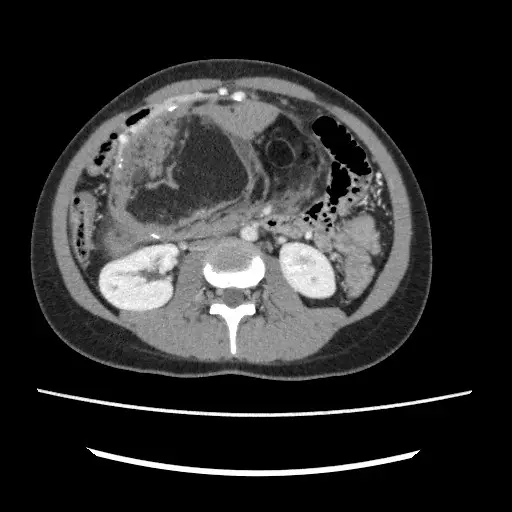

Figure 15: CT scans are useful when a detailed assessment is needed to evaluate a known or suspected pathology where an ultrasound is insufficient. CT scans can also be used as the primary modality for suspected malignancy or if surgery might be required later. The figure above shows an abdominal and pelvic CT scan revealing a large benign ovarian tumor in a patient presenting with abdominal fullness, swelling, bloating, and reduced appetite.